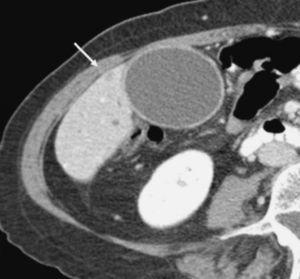

Aunque algunos autores no han observado diferencias significativas en cuanto al rendimiento de la TC helicoidal monofásica y bifásica en la detección y estadificación del cáncer de páncreas13, otros autores19,32, en series más largas incluyendo un mayor número de pacientes con tumores resecables, han aseverado el rendimiento de la TC helicoidal bifásica en la predicción de la resecabilidad del cáncer de páncreas, presentando valores predictivos para la resecabilidad tumoral entre 73,5% y 77% y valores de precisión diagnóstica entre 77% y 83%. Revisando específicamente los signos TC de infiltración vascular mediante TC helicoidal bifásica, Lu et al33, utilizando un sistema de gradación basado en la contigüidad del tumor con cada una de las estructuras vasculares (venas porta y mesentérica superior, o arterias hepática, mesentérica superior y tronco celíaco), presentaron un valor predictivo positivo del 95% y un valor predictivo negativo para la irresecabilidad neoplásica del 93% cuando consideraban infiltración vascular una contigüidad del tumor que excedía el 50% de la circunferencia del vaso en cuestión (fig. 4). A este mismo respecto Phoa et al34 describen como criterios de TC más fiables de invasión venosa la estenosis e irregularidad de la vena porta o la vena mesentérica superior, así como una contigüidad circunferencial del tumor con la vena porta superior a 90º (fig. 5). Los autores concluyen que la mejor combinación de criterios de TC fue la concavidad tumoral con afectación circunferencial vascular, con lo que presentan una sensibilidad del 61% y especificidad del 90%. Hough et al35 describieron el signo de la lágrima de la vena mesentérica superior, que consiste en una deformidad de la morfología redondeada de la vena adyacente al tumor en las secciones axiales, como indicativo de invasión venosa (fig. 6). Añadiendo este signo a los ya descritos de invasión venosa, consiguen aumentar la sensibilidad (60-91%) y el rendimiento diagnóstico de la TC (79-95%) sin modificar significativamente la especificidad (100-98%). No obstante, estos sistemas de gradación para el diagnóstico de la invasión vascular peripancreática tienen el inconveniente de la subjetividad a la que está sometida su lectura. Los casos extremos no presentan problemas de interpretación, pero la valoración del tumor rodeando al vaso alrededor de 90º de su circunferencia puede ser difícil, dado que además pueden existir bandas de infiltración de la grasa peripancreática que pueden rodear parcialmente un vaso o incluso continuarse sin plano graso de separación con el tejido tumoral. Estas bandas pueden representar cambios edematosos o inflamatorios locales (fig. 7). En este sentido, Valls et al19,36 presentan únicamente un 25% de valor predictivo positivo para la irresecabilidad tumoral para estas bandas perivasculares. Además se ha descrito la notoria variabilidad interobservador en función de su experiencia, que llega a alcanzar una diferencia de sensibilidad de hasta un 20% entre revisores experimentados y noveles14.

Fig. 5.--Adenocarcinoma de páncreas. Estudio de tomografía computarizada con contraste endovenoso en fase pancreatográfica. Masa de 5 cm al nivel de la cabeza pancreática que contacta ampliamente con la vena mesentérica superior (VMS) en aproximadamente 50° de su circunferencia, sin deformarla ni disminuirla de calibre. En la intervención quirúrgica se confirmó la invasión de la VMS, realizándose resección con interposición de injerto venoso.